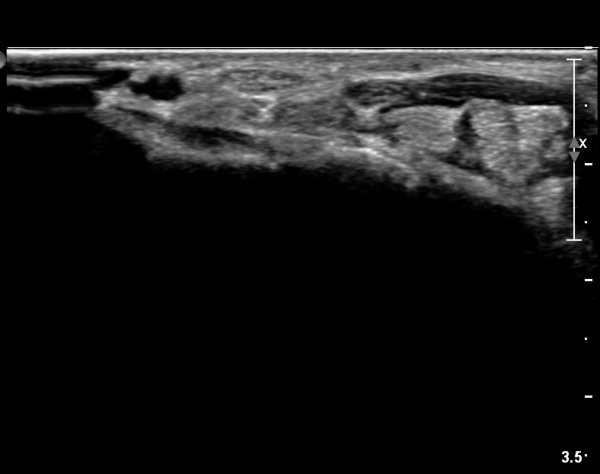

ÀÌ·± ¸ð½ÀÀº ¼Õ¸ñÀÇ ¿ù»ó°ñ ºÎÀ§(»çÁø 3, 4)¸¦ Áö³ª ¼ö±Ù°ü ±ÙÀ§ºÎ ±îÁö À̾îÁü(»çÁø 5).

ÇÏŰ½ºÆ½(°íÁÖÆÄ) ŽÃËÀÚ¸¦·Î °üÂûµÈ ¸ð½À¿¡¼­ Á¤Áß½Å°æ ºÎºÐ ½Å°æ´Ù¹ßÀÇ Àú¿¡ÄÚ

º¯È­°¡ ¶Ñ·ÈÇÔ(»çÁø 6, 7).

Á¤Á߽Űæ Á¾´Ü¸é°Ë»ç¿¡¼­µµ ¼Õ¸ñ ¸»´ÜºÎ¿¡¼­ ¼ö±Ù°ü ±ÙÀ§ºÎ±îÁö À̾îÁø Àú¿¡ÄÚ

Á¾¾çÀÌ °üÂûµÊ(»çÁø 8, 9, 10, 11).